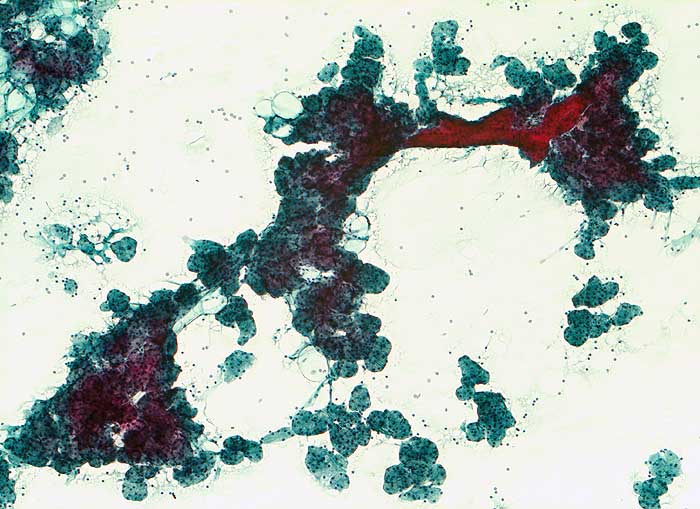

Feinnadelpunktion Parotis: hypertrophe runde Drüsenazini mit rotem Schaltstück. Die Azinuszellen sind deutlich vergrössert zytoplasmareich.

Histologie: Chronische obstruktive Sialadenitis mit Fibrose und Atrophie der Drüsenazini

Endokarditis. Kathetersepsis. Leberzirrhose. Parotisschwellung beidseits.

Nicht neoplastische Vergrösserung der Speicheldrüsen. Zytologisch lässt sich die Diagnose aufgrund des klinischen Hintergrundes und des Fehlens neoplastischer oder entzündlicher Veränderungen stellen.